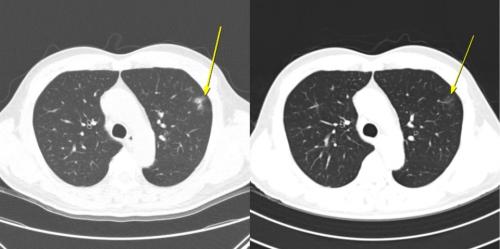

¹«Áõ»ó ÀϽÃÀû ¸é¿ª°ü·Ã Æó·Å »ç·Ê: ÀÌ È¯ÀÚ´Â AteBeva Ä¡·á 3°³¿ù° ½ÃÇàÇÑ Àú¼±·® ÈäºÎ CT(¿ÞÂÊ)¿¡¼­ Æó ÁÖº¯ºÎ¿¡ ¹Ì¼¼ ¿°Áõ¼º À½¿µÀÌ ³ªÅ¸³µÀ¸³ª, 6°³¿ù° CT(¿À¸¥ÂÊ)¿¡¼­´Â ÀÚ¿¬ÀûÀ¸·Î ¼Ò½ÇµÇ´Â ¾ç»óÀ» º¸¿´´Ù. Ä¡·á´Â Áö¼ÓµÆÀ¸¸ç, ÀÌÈÄ ºÎºÐ °üÇØ(PR)¸¦ ´Þ¼ºÇß°í ÃÑ 19.7°³¿ù°£ ¹«ÁøÇà »ýÁ¸(PFS)À» À¯ÁöÇß´Ù.

¿¬±¸ÆÀÀº Ä¡·á Áß ³ªÅ¸³­ ÀÌ»ó¹ÝÀÀ ¾ç»ó¿¡ µû¶ó ȯÀÚ¸¦ ÀÌ»ó¹ÝÀÀÀÌ ÀüÇô ¾ø´Â ‘¹«ÀÌ»ó¹ÝÀÀ±º’ ÀÓ»ó Áõ»óÀ̳ª Ç÷¾×°Ë»ç ÀÌ»óÀ» µ¿¹ÝÇÑ ‘Áõ»ó¼º ÀÌ»ó¹ÝÀÀ±º(Áõ»ó±º)’ Áõ»óÀº ¾øÁö¸¸ CT¿¡¼­ Æó ÁÖº¯ºÎ ¹Ì¼¼ ¿°Áõ¼º À½¿µ, ÀϽÃÀû ´ëÀ庮 ºñÈÄ, Àå°£¸· ¿°Áõ, ¹ÝÀÀ¼º ¸²ÇÁÀý Á¾´ë µî ¸é¿ª¹ÝÀÀÀ¸·Î ÇØ¼®µÇ´Â º¯È­¸¸ ³ªÅ¸³­ ‘¹«Áõ»ó ¿µ»ó ÀÌ»ó¹ÝÀÀ±º(¹«Áõ»ó ¿µ»ó±º)’À¸·Î ºÐ·ùÇß´Ù. Àüü 198¸í Áß ¹«Áõ»ó ¿µ»ó±ºÀº 12¸í, Áõ»ó±ºÀº 56¸í, ¹«ÀÌ»ó¹ÝÀÀ±ºÀº 130¸íÀ̾ú´Ù.